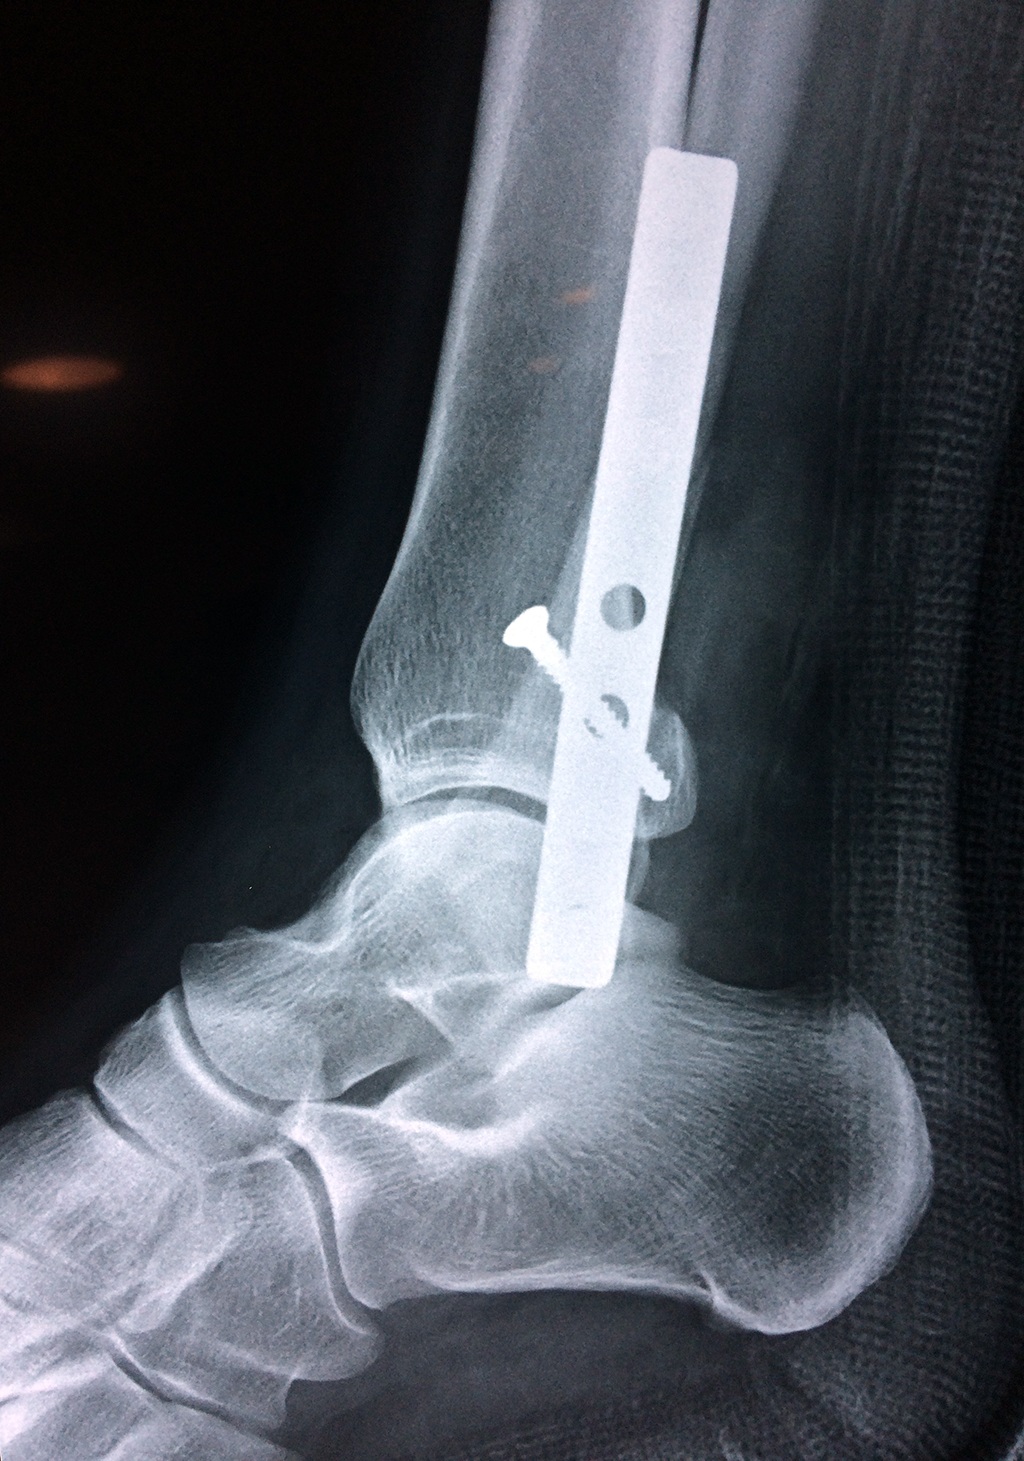

Cuando se necesita cirugía, es probable que esta implique el uso de clavijas de metal, tornillos o placas para sostener los huesos en su lugar mientras la fractura se consolida. Los elementos de soporte pueden ser temporales o permanentes.

Algunas fracturas de tobillo pueden requerir cirugía si:

- Los extremos de los huesos están desalineados entre sí (desplazados).

- La fractura se extiende hasta la articulación del tobillo (fractura intra-articular).